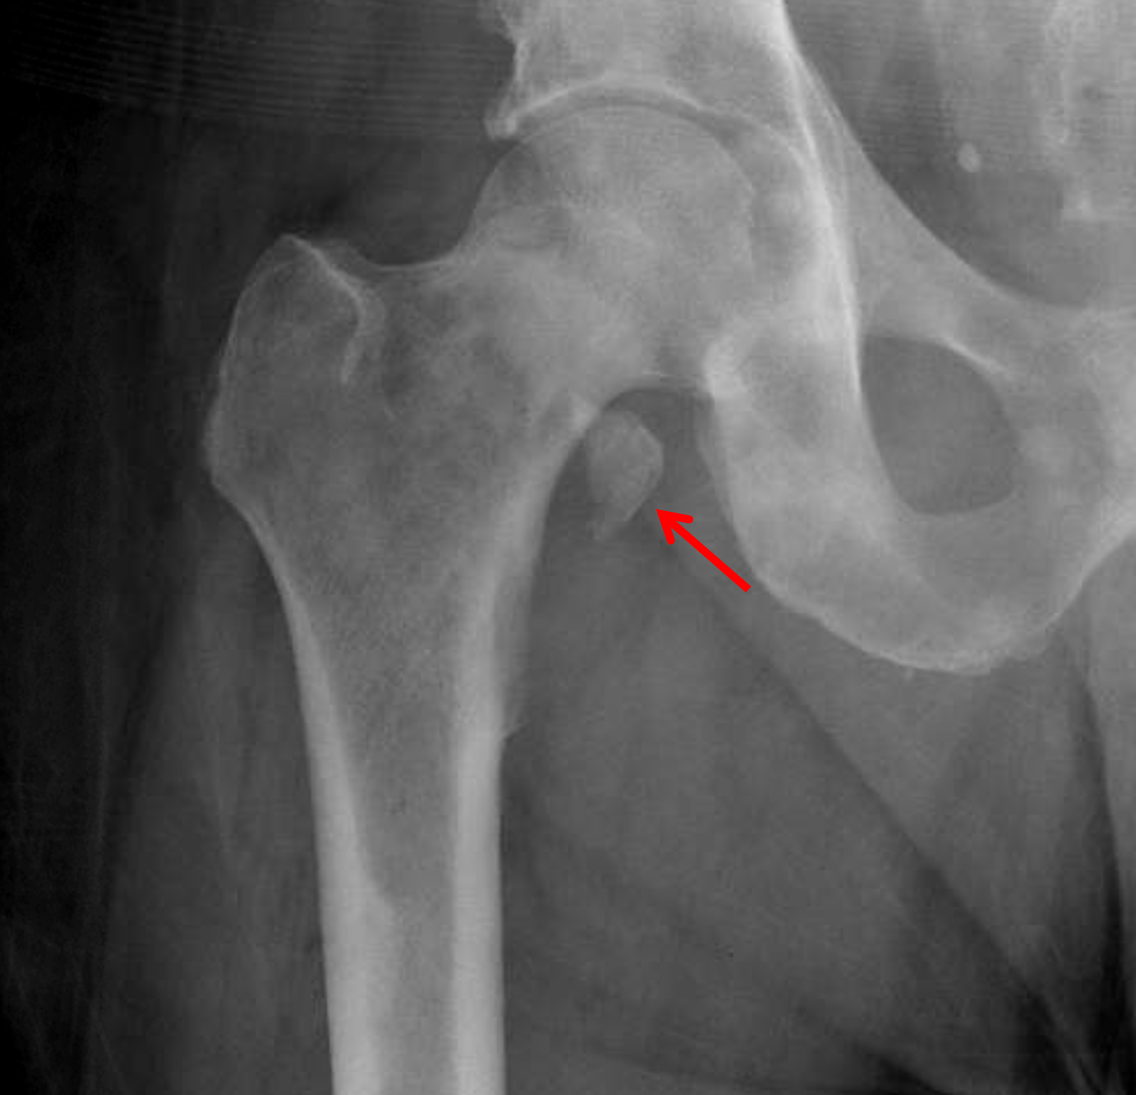

Lesser Trochanter Avulsion Fracture Radiology : Arthroscopic treatment for a chronic isolated avulsion ... : The position of the lesser trochanter close to the head of the femur is one of the defining characteristics of the prozostrodontia.. Avulsion fractures of the lesser trochanter, greater trochanter, and iliac crest are less common.5 although not as common as other avulsions in the pelvis, lesser trochanter avulsion causes considerable pain and decreased function. The position of the lesser trochanter close to the head of the femur is one of the defining characteristics of the prozostrodontia. This new sporting activity involves kicking. In an older patient, rule out pathological metastatic fracture. Avulsion fracture of left lesser trochanter at the insertion of the iliopsoas tendon.

They are a result of a sudden and forceful contraction of the iliopsoas muscle. This new sporting activity involves kicking. This can occur at the ligament by the application of forces external to the body (such as a fall or pull). Avulsion fractures of the lesser trochanter, greater trochanter, and iliac crest are less common.5 although not as common as other avulsions in the pelvis, lesser trochanter avulsion causes considerable pain and decreased function. Ap (a, c) and oblique (b,d) radiographs of the right ankle demonstrate a prominent well corticated (black arrows) ossicle (white arrows) adjacent to the distal fibular tip consistent with a remote avulsion. Isolated fractures of the lesser trochanter are. We report the case of a skeletally immature freestyle footballer who presented with avulsion fracture of the lesser trochanter. Isolated lesser trochanter fractures are a rare presentation of hip fractures in elderly adults.

Avulsion fractures on this region are generally secondary to strenuous physical activities 1. Isolated fractures of the lesser trochanter are rare in adults and usually represent the initial manifestation of skeletal metastatic disease (figure 5). Avulsion in adolescence is probably due to avulsion of the iliopsoas tendon. They are generally caused by a sudden and forceful contraction of the iliopsoas muscle. There is fluid and hematoma around the iliopsoas tendon. Isolated fractures of the lesser trochanter are reported to be pathognomic for tumor diseases in adults. By itself, this avulsion is of no importance, but it sometimes. This injury is a result of a sudden forceful contraction of the iliopsoas tendon. They are a result of a sudden and forceful contraction of the iliopsoas muscle. Isolated lesser trochanter fractures are a rare presentation of hip fractures in elderly adults. Ap (a, c) and oblique (b,d) radiographs of the right ankle demonstrate a prominent well corticated (black arrows) ossicle (white arrows) adjacent to the distal fibular tip consistent with a remote avulsion. A recent case series (of only five patients) showed that the mean age of patient that presented with this injury. Avulsion of the lesser trochanter.

Chronic avulsion fracture of the anterior inferior iliac spine, origin of the straight head of the rectus femoris muscle lesser trochanter fracture. Lesser trochanter avulsion fracture � pathologic.